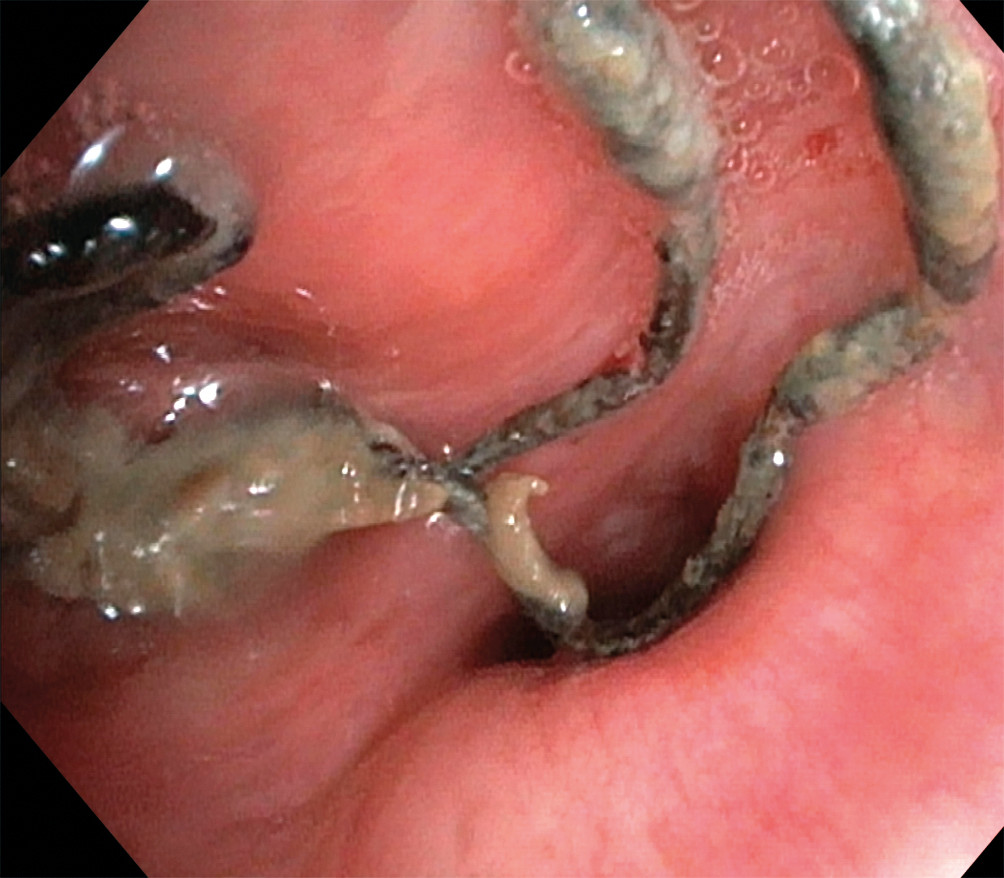

På bildet, tatt ved bronkoskopi, ses suturmateriale og purulent slim som ligger endobronkialt, nær ostiet for det apikale underlappssegment på høyre side.

Pasienten er en kvinne i 50-årene. Som barn ble hun operert med partiell høyresidig underlappsektomi. Man lot det apikale underlappssegmentet stå igjen, og det ble brukt ikke-resorberbar tråd. Etter operasjonen har hun hatt tilbakevendende nedre luftveisinfeksjoner, alt fra bronkitt til pneumoni. Forut for den aktuelle bronkoskopien ble det gjort CT thorax som avdekket abscessutvikling (CT-bilde). Ved utredning fant man ingen underliggende immunsvikt eller andre forklaringer på infeksjonstendensen. Hun røyker daglig, men har ingen obstruktiv lungesykdom. Suturmaterialet som ble avdekket ved bronkoskopi var i retrospekt synlig på CT thorax-bildet, men kunne muligens mistolkes som sekret i luftveiene.

Suturmateriale er som et fremmedlegeme og fremmer dannelse av en biofilm og bakteriekolonisering. Dette er høyst sannsynlig årsaken til gjentatte pneumonier og utviklingen av lungeabscess (1). De synlige suturene lot seg fjerne med tang bronkoskopisk. Prosedyren ble gjort først etter at pasienten hadde gjennomført langvarig antibiotikabehandling. Selv om det hadde gått mer enn 40 år siden operasjonen fant sted, var ikke suturmaterialet brutt ned. I litteraturen har vi funnet bare få rapporter om fjerning av aspirert fremmedlegeme med tilsvarende tidsspenn fra aspirasjon til fjerning (2). I disse tilfellene har indikasjonen for utredningen vært tilbakevendende pneumonier, slik som hos vår pasient. Det vi kan lære av kasuistikken, er at hos pasienter med gjentatte nedre luftveisinfeksjoner av ukjent årsak bør man vurdere CT thorax og bronkoskopi.